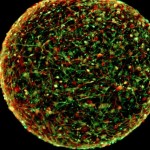

Scientists think they can make a mini, thinking version of your brain with just a few skin cells

Tiny, rolling balls of brain cells knocking around in a lab may one day help keep you from losing your marbles—among other things. … [Read more...]